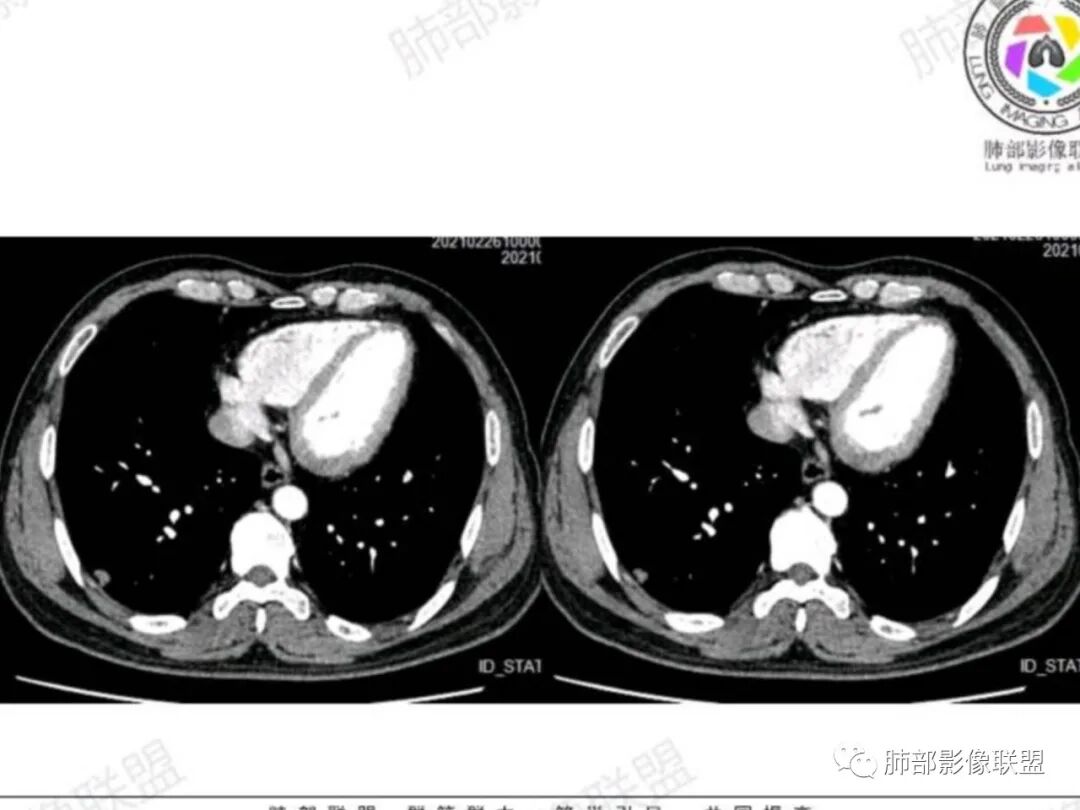

右肺下叶胸膜下实性小结节,呈条状,长轴平行胸膜,宽基底与胸膜相贴,病灶边缘毛糙,胸膜侧可见U型凹陷,轻度牵拉胸膜,平扫密度均匀,增强扫描后中度强化,单发孤立性结节,中年男性,体检发现,建议先隐球菌荚膜实验,阴性考虑腺癌可能性大,必要时建议短期随访,

支持恶性 年龄,类圆形结节,整体膨隆,强化。支持良性,无分叶毛刺空泡,无磨玻璃,病灶边缘似乎有些平直,宽基底和胸膜相链,无侵犯,收缩力弱,支气管关系不明确,纵隔淋巴结不大

右肺下叶胸膜下实性山丘状结节影,密度均匀,边缘可见棘状突起,结节胸膜侧收缩,见胸膜凹陷征。周围无磨玻璃及卫星病灶,增强后结节轻-中等强化。考虑腺癌可能,肉芽肿性炎待排。

右肺下叶后基底段胸膜实性结节,不均匀轻_中强化,见小湖泊样坏死,坏死轮廊不清,形态不规则,边缘见短小毛刺,有胸膜下浸润征,考虑肺Ca(小细胞?),与炎性结节鉴别,建议穿刺活检!

老年男性,右下肺近胸膜结节影,边界清,边缘部分膨隆,不均匀强化,可见坏死,可见脐凹,血管进入,血管扩张,未见明确支气管影,考虑恶性,腺癌可能,鉴别隐球菌、小细胞

老年男性,右肺下叶胸膜下孤立实性结节,边缘平直凹陷+膨隆,胸膜下脂肪间隙增宽,空洞型胸膜凹陷,中度较均匀强化,与支气管关系不明确。考虑炎性肉芽肿>癌

右侧胸膜下实性结节,边缘毛刺,膨隆,强化,考虑炎性结节鉴别腺

男性,53岁,体检发现右肺下叶胸膜下小结节,整体膨隆,宽基底与胸膜相连,不均匀强化,内部似见坏死区,局部层面似见小尾巴,考虑恶性可能,腺癌或小细胞

老年男性,右肺下叶胸膜下结节,有膨胀性和收缩性,可见短毛刺,胸膜凹陷征,血管穿入结节内,不均匀强化。考虑恶性病变,腺癌可能。鉴别隐球感染。

紧贴胸膜实性结节,边缘毛糙,轻强化,有坏死,坏死边缘不清,形态不规则,胸膜浸润,考虑小细胞,鉴别腺癌。

男,63,体检发现肺部结节。胸部CT:右肺下叶胸膜下类圆形实性结节影,边界清楚,边缘膨隆、短毛刺,细支气管在病灶边缘截断,小血管进入,胸膜牵拉圆洞样凹陷,胸膜外脂肪间隙增宽。增强密度不均匀,内有点状低密度。引流区域淋巴结增大?考虑恶性,腺?小?鉴别PC、TB等肉芽肿。